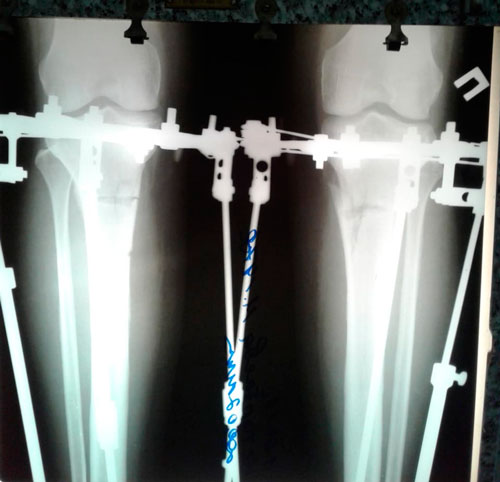

Дата операции - 05.03.2019г.

Дата снятия аппаратов - 26.06.2019г.

Срок сращения - 110 дней.